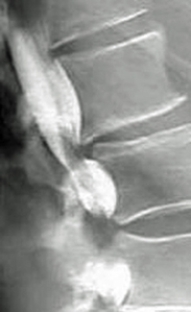

Which of the following imaging techniques illustrated in the pictures would be the most efficient to discover if there is a loose body within a joint?

Q15: Which of the following imaging techniques illustrated

Q17: Which of the following imaging techniques illustrated